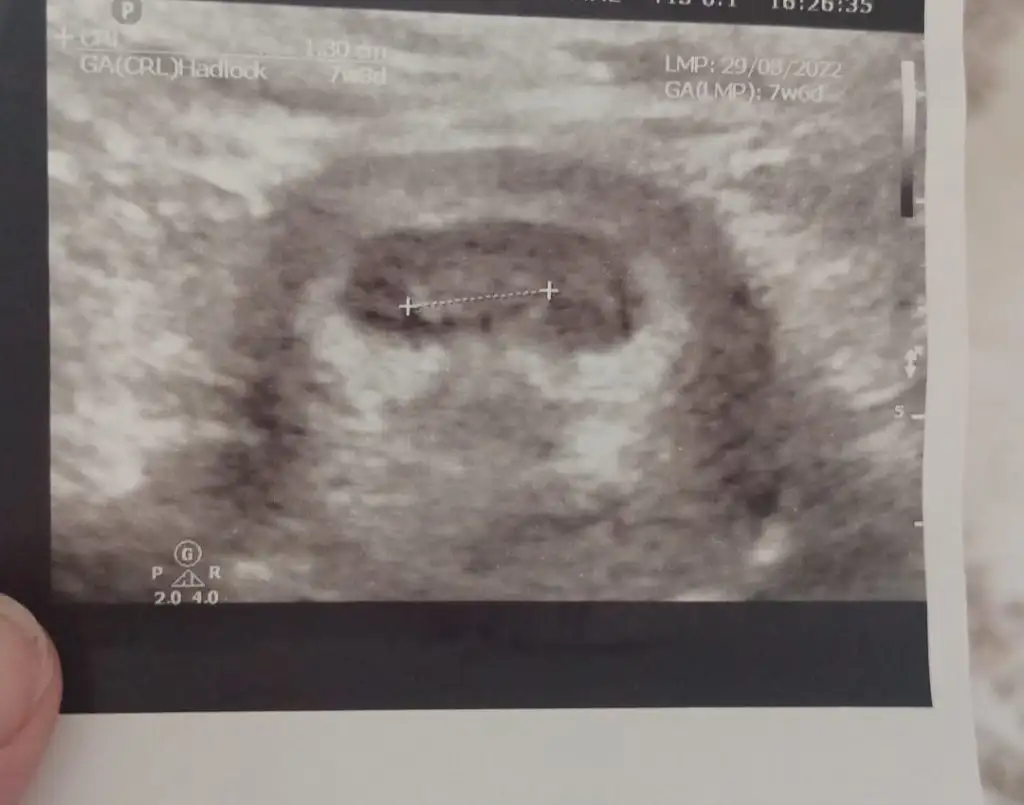

prenses gibiBu da bi arkadaşımın bebegi 12 hastalıkmış karindan

11 hafta 1 günlük karından bu da arkadaşımın yorumlarsanız sevinirim :)Selam Kızlarbir çok kişi gruplardan beni bilir. Yine yetiştim imdatlara